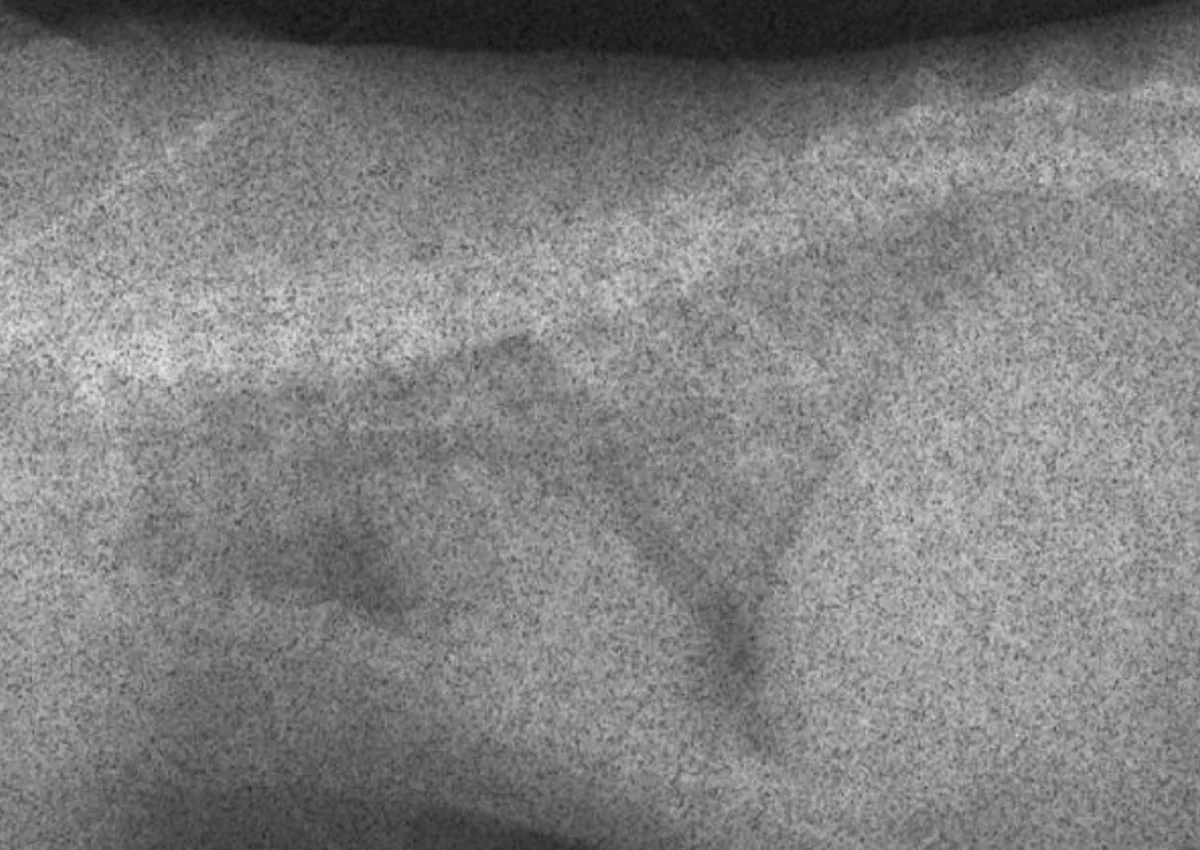

If you are using a digital radiography system, the software attempts to adjust brightness to correct for over- and underexposure. If a digital image is severely underexposed, however, the digital system cannot correct for it. The resulting image will look very grainy, as in this example of a cat thorax that was extremely underexposed (Figure A). Figure B shows the corrected technique.